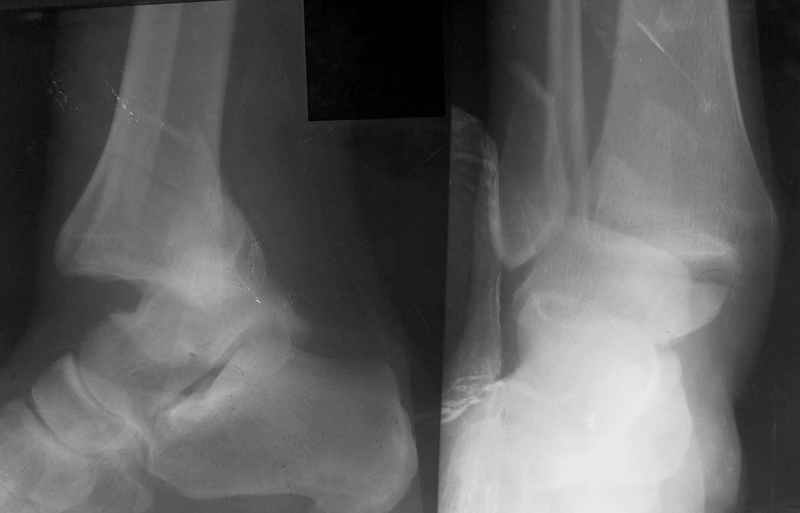

Стабильность г\ст сустава обеспечивается во-первых наружной лодыжкой (ключ), во-вторых задним краем б\б кости, в-третьих связками синдесмоза и межкостной мемраной, только в-четвертых медиальной лодыжкой (дельтовидной связкой. Это классика! А пяточной кости и плюсневых костей здесь нет! зачем их фиксировать? см. вложенный файл.